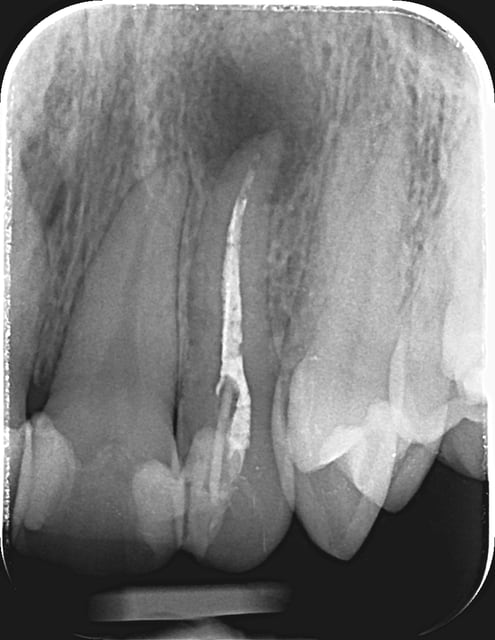

1) Video cas - retirer instrument fracturé

https://www.facebook.com/photo.php?v=646019828781877

2) Retraitement après 10 ans avec enlèvement de l'instrument fracturé

09/01/2014 à 01h54

07/05/2014 à 11h10

Initial e après obturation

no !!! condensation latérale à froid est alors verticale chaud... e buildup